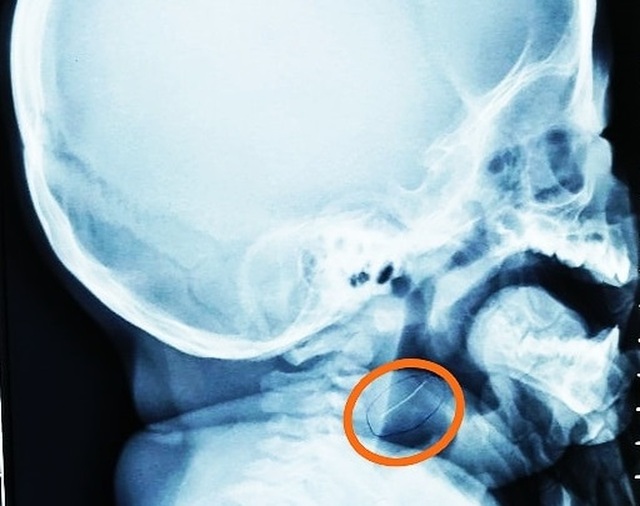

Tại đây, bác sĩ đã cho bé chụp X-quang cổ nghiêng thì phát hiện một vật cản quang có hình dạng rất mảnh đang nằm ở hầu họng. Ngay lập tức, bác sĩ cho bé thực hiện nội soi khẩn cấp gắp dị vật. Bằng thiết bị nội soi chuyên dụng cho bệnh nhi, bác sĩ đã gắp ra một sợi kim loại mảnh nhưng rất cứng và nhọn 2 đầu, dài gần 2cm.

Bác sĩ chuyên khoa 2 Trần Thiện Nhơn, khoa Tai Mũi Họng cho biết, sợi kim loại đã cắm sâu vào vùng hạ họng tương đương với 1/3 chiều dài khiến bệnh nhi đau đớn. Nhưng may mắn cho bé vì dị vật chưa xuống sâu hơn nên không gây ra những ảnh hưởng nguy hiểm đến sức khỏe. Tuy nhiên nếu không được phát hiện gắp ra kịp thời, đoạn kim loại có thể xuyên thủng đường tiêu hóa dẫn đến những hậu quả khó lường.